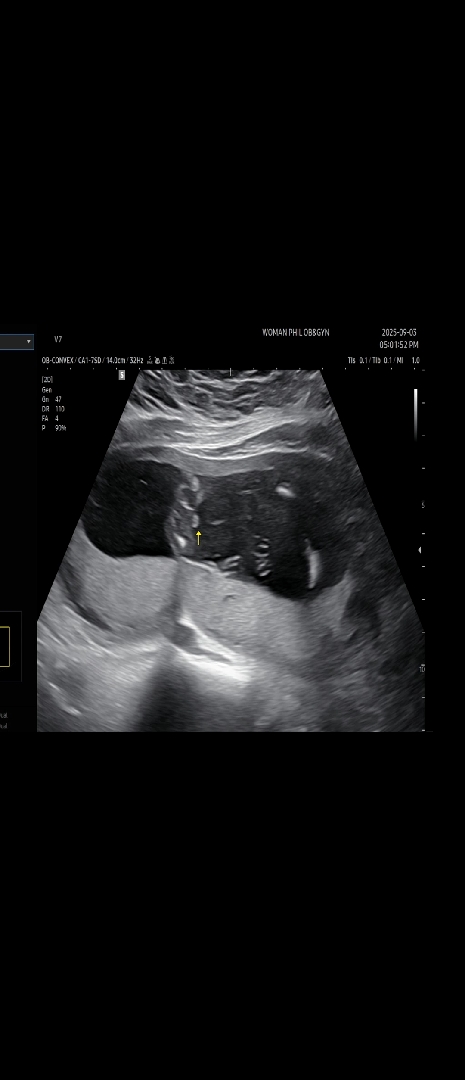

신랑은 너무 딸을 원하는데 16주3일인 오늘, 의사쌤이 "고추가 보인다 아들인것 같다~ 근데 내가 잘못봤으면 20주차에 알게되겠지~" 하셨거든요 아들들 초음파 보면 꼬추가 우리애기보다 더 확실하던데 여러분들 보시기엔 쌤이 잘못보셔서 딸일 가능성 있어 보이나용?

제가 17주인데 저희애기가 아들인데 아들생식기는 저렇지않아요.. 딸같은데요??